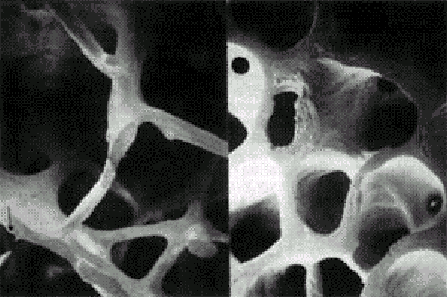

Остеопороз (ОП) – системное заболевание, характеризующееся уменьшением костной массы и нарушением микроархитектоники костей, ведущими к повышенной хрупкости костей и появлению переломов(рис. 1).

Рисунок 1. Микроархитектоника здоровой (слева) и остеопоретической (справа) трабекулярной кости.